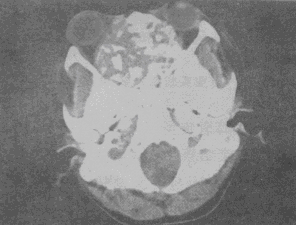

男,26岁,进行性鼻腔阻塞、流涕来院就诊,近两年持续性头痛、头晕,筛窦区病变影像检查如图,最可能的诊断是

A.脊索瘤伴左上颌窦炎

B.软骨瘤伴左上颌窦炎

C.骨化性纤维瘤伴左上颌窦炎

D.骨结核伴左上颌窦炎

E.骨纤维异常增殖症伴左上颌窦炎

男,26岁,进行性鼻腔阻塞、流涕来院就诊,近两年持续性头痛、头晕,筛窦区病变影像检查如图,最可能的诊断是<img border="0" style="width:

[单选题]男,26岁,进行性鼻腔阻塞、流涕来院就诊,近两年持续性头痛、头晕,筛窦区病变影像检查如图,最可能的诊断是A.脊索瘤伴左上颌窦炎B.软骨瘤伴左上颌窦炎C

男,26岁,进行性鼻腔阻塞、流涕来院就诊,近两年持续性头痛、头晕,筛窦区病变影像检查如图,最可能的诊断是()<img border="0" style="width

[单选题]男,26岁,进行性鼻腔阻塞、流涕来院就诊,近两年持续性头痛、头晕,筛窦区病变影像检查如图,最可能的诊断是()A.脊索瘤伴左上颌窦炎B.软骨瘤伴左上颌窦

男,26岁,进行性鼻腔阻塞、流涕来院就诊,近两年持续性头痛、头晕,筛窦区病变影像

[单选题]男,26岁,进行性鼻腔阻塞、流涕来院就诊,近两年持续性头痛、头晕,筛窦区病变影像检查如图,最可能的诊断是()A . 脊索瘤伴左上颌窦炎B . 软骨瘤伴左上颌窦炎C . 骨化性纤维瘤伴左上颌窦炎D . 骨结核伴左上颌窦炎E . 骨纤维异常增殖症伴左上颌窦炎

男,26岁,进行性鼻腔阻塞、流涕来院就诊,近两年持续性头痛、头晕,如图所示筛窦区

[单选题]男,26岁,进行性鼻腔阻塞、流涕来院就诊,近两年持续性头痛、头晕,如图所示筛窦区占位灶应诊断为()。A . 脊索瘤伴左上颌窦炎B . 软骨瘤伴左上颌窦炎C . 骨化性纤维瘤伴左上颌窦炎D . 骨结核伴左上颌窦炎E . 骨纤维异常增殖症伴左上颌窦炎

男,26岁,进行性鼻腔阻塞、流涕来院就诊,近两年持续性头痛、头晕.如图所示筛窦区

[单选题]男,26岁,进行性鼻腔阻塞、流涕来院就诊,近两年持续性头痛、头晕.如图所示筛窦区占位灶应诊断为()A .脊索瘤伴左上颌窦炎B .软骨瘤伴左上颌窦炎C .骨化性纤维瘤伴左上颌窦炎D .骨结核伴左上颌窦炎E .骨纤维异常增殖症伴左上颌窦炎